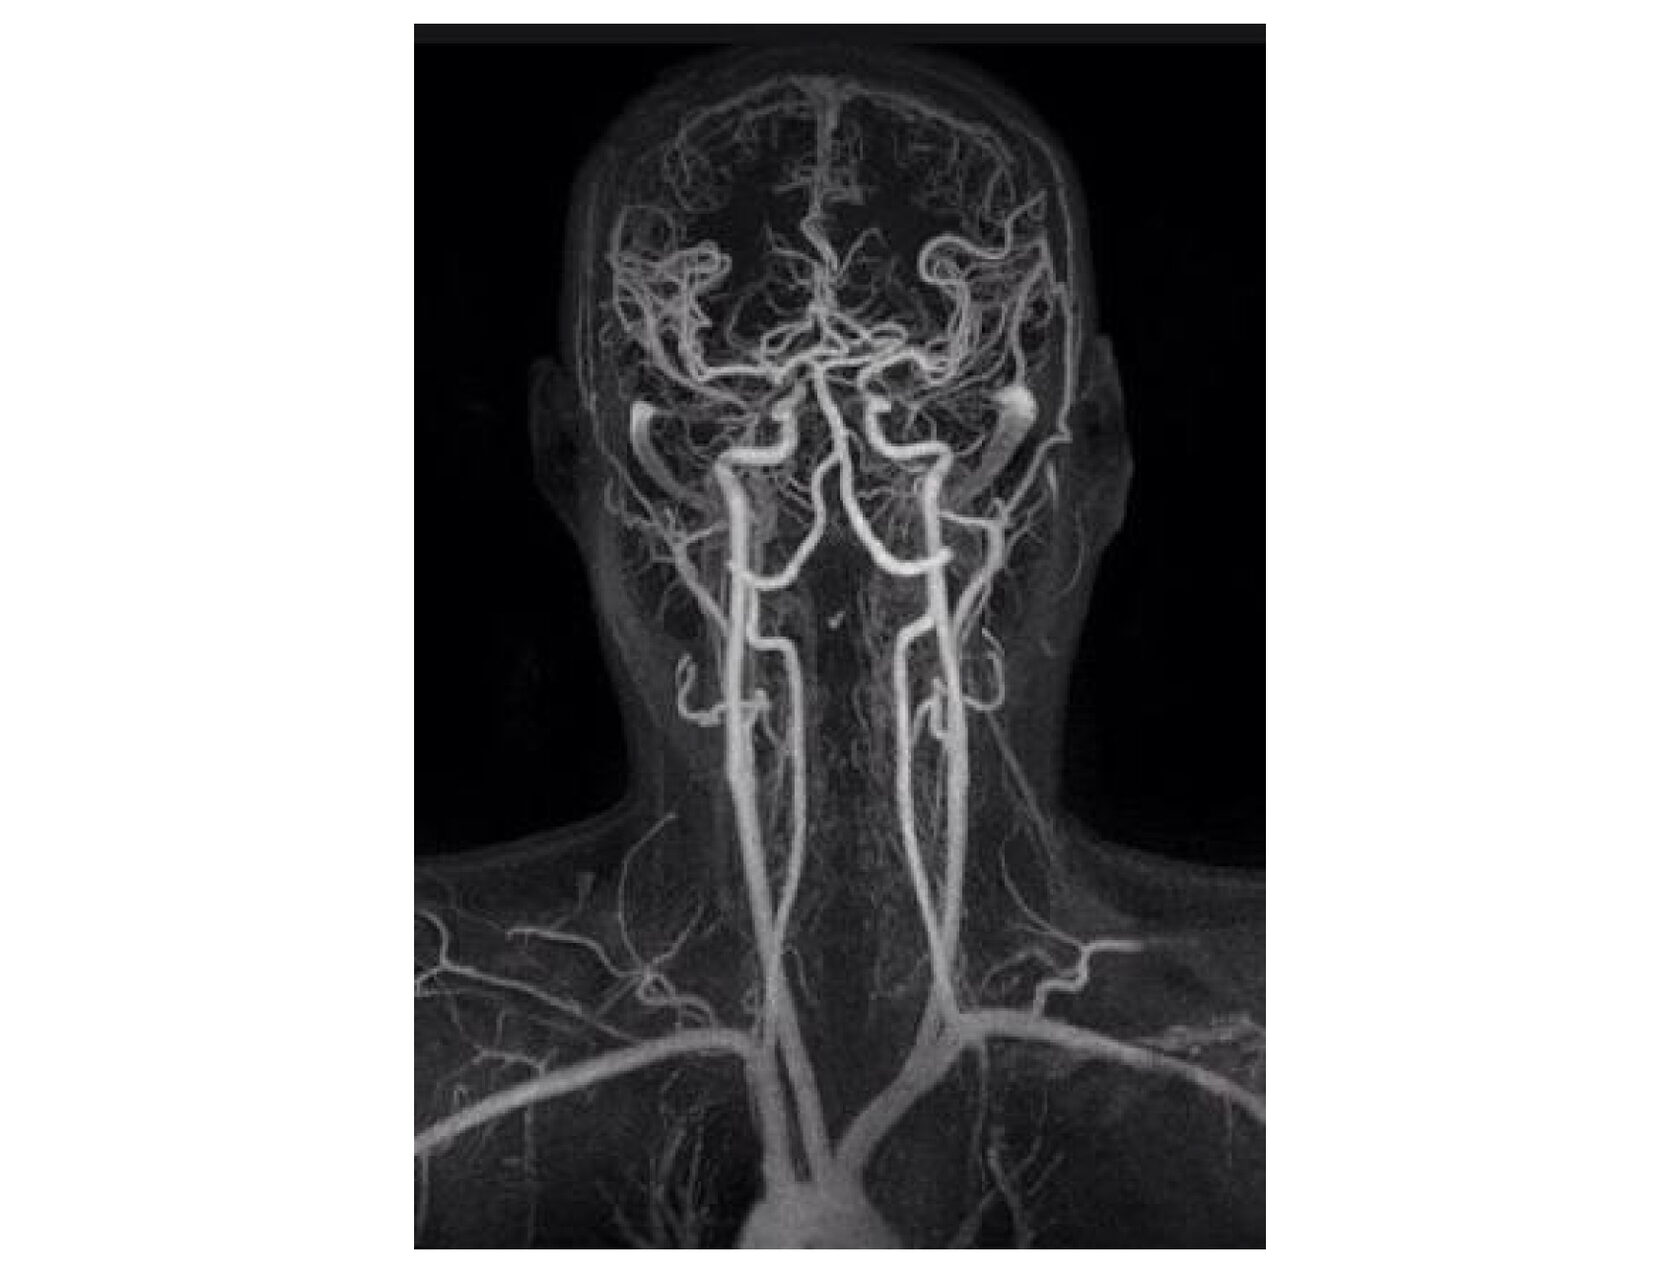

Пациент со здоровыми позвоночными артериями

Большинство пациентов с подобными жалобами как ПА имеют клинически здоровый шейный отдел позвоночника. Анатомически невозможно, чтобы остеофиты, грыжи или смещение атланта сдавливали сосуды шеи до степени, способной вызвать значимое нарушение кровоснабжения.